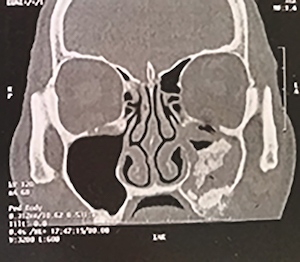

Dans le détail, Jean-François Papon, médecin chef du service ORL au centre hospitalier universitaire du Kremlin-Bicêtre, ouvrira cette journée avec la présentation des fondamentaux. Il rappellera les subtilités anatomiques du sinus et nous apprendra à repérer, grâce au bon examen radiographique, les images types à ne pas manquer.

- Lecture de l’imagerie sinusienne : repérer les structures et anomalies anatomiques

- Analyse radiographique préopératoire en implantologie

- Savoir analyser les radiographies sinusiennes